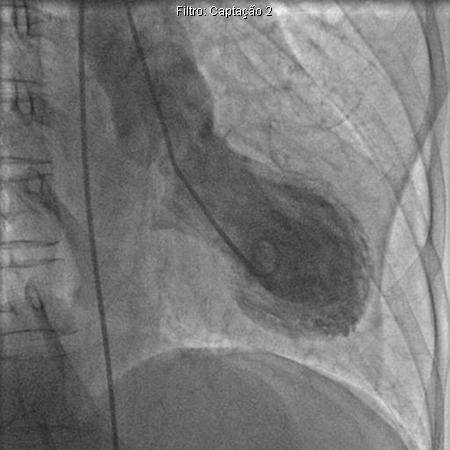

Ventriculograma esquerdo demonstrando balonamento apical na cardiomiopatia de Takotsubo

Augustine DX, Domanski A, Garg A. The stress of chest pain: a case of tako-tsubo cardiomyopathy. BMJ Case Reports. 2009; doi:10.1136/bcr.03.2009.1660